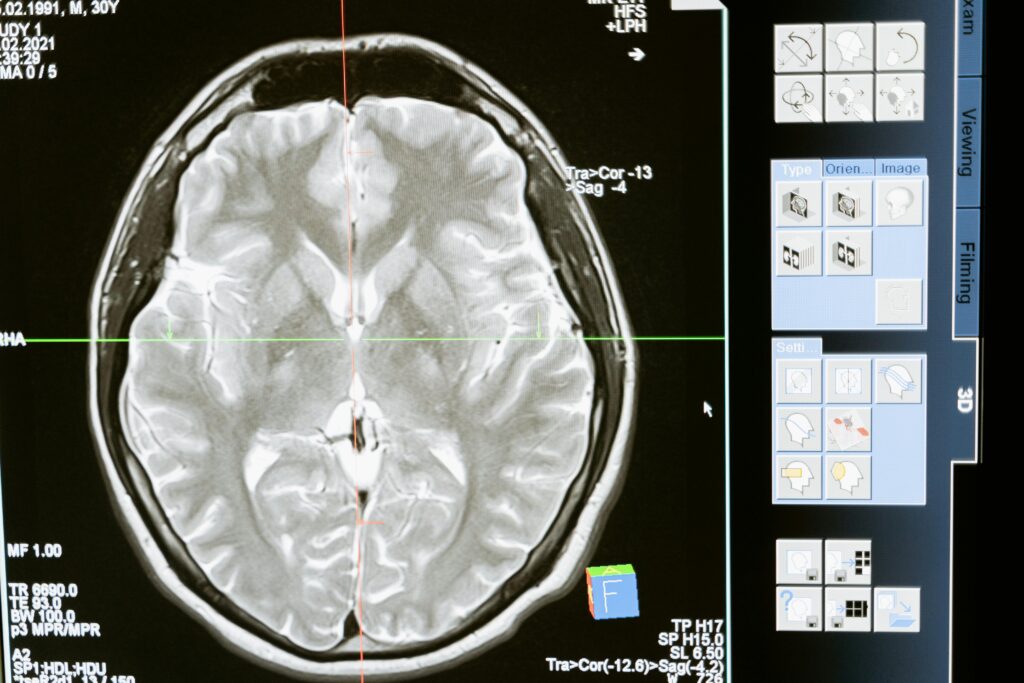

L’épilepsie est une maladie neurologique provoquant des crises imprévisibles : spasmes, hallucinations, troubles moteurs ou pertes de conscience. Dans les cas les plus sévères, une intervention chirurgicale du cerveau peut être nécessaire.

L’intelligence artificielle apporte alors une aide précieuse aux neurochirurgiens, en identifiant avec précision les zones à opérer et les voies d’accès les plus sûres, minimisant ainsi les risques de séquelles.

C’est dans ce contexte que j’ai eu l’opportunité de collaborer avec l’Hôpital de la Timone et l’Institut de Neurosciences des Systèmes (INS).